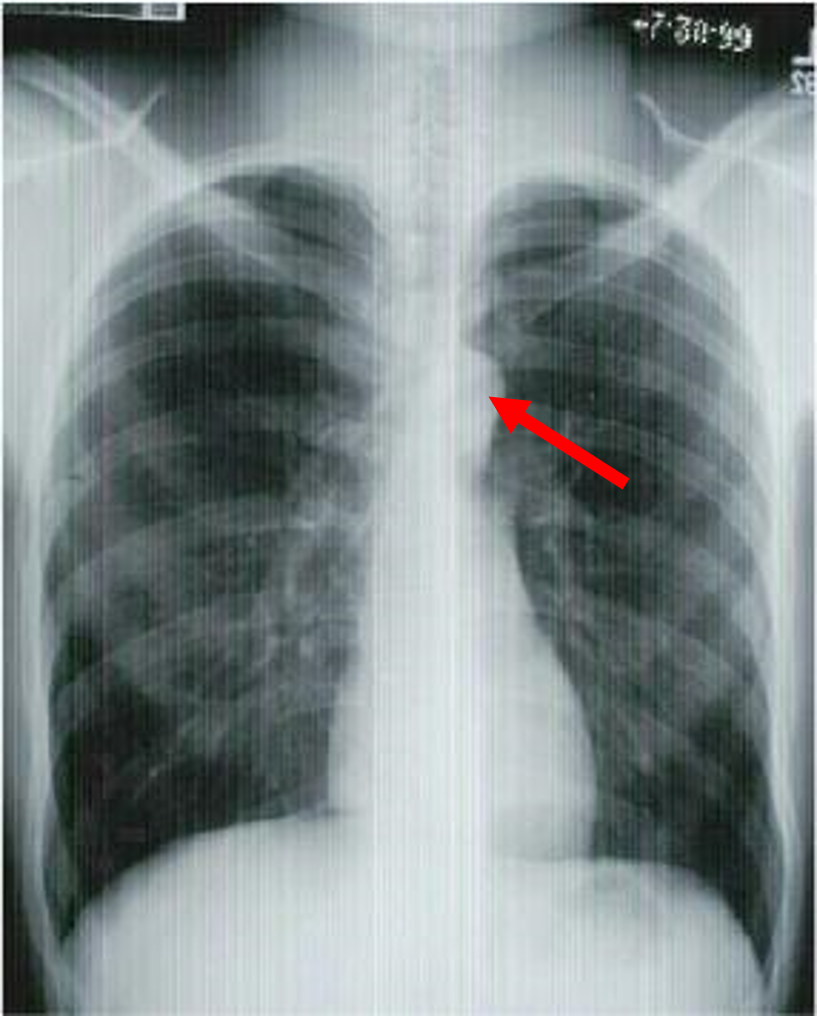

what view is this?

three indentifiers

how far is the xray source from the plate in an AP? PA? Lateral?

AP is 3 feet

PA is 6 feet

lateral is 6 feet

aortic arch

pulmonary artery